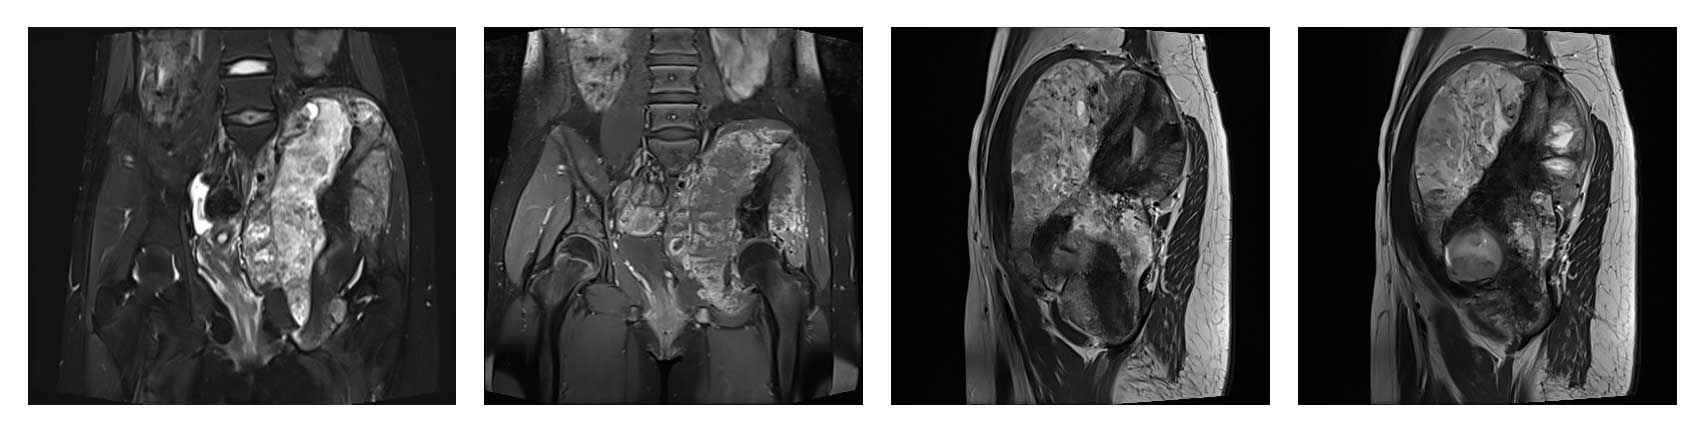

Ameliyat Öncesi: MR’da lomber 5. vertebra, sakrum ve iliak kanatın tamamını tutan kemikte harabiyete neden olup yumuşak dokuya uzanan büyük tümör dokusu görülmekte.